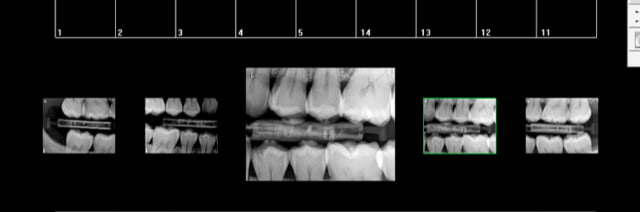

Et là ?

Alors en 1 rétro-coronaires puis en 2 rétro alvéolaires si une pathologie pulpaire est suspectée ( caries et reconstitutions larges et profondes)

Jouons la sécurité......... qui peut le plus peut le moins. -)

7 radios?

8 tu passes les 34 et 44 en rétro coronaires ( car rétro alvéolaires non justifiées.)

Lol et re lol !-)))

Par contre je me demande si j'aurais pas du prendre les canines du haut et avoir les sagesses complètes. -)

la notion de reconstitution large et profonde et celle de carie pénétrante reste à définir. -)

Total des courses dans pas mal de cas je fais plus de cliché qu'avant car en plus des rétro alvéolaires je fais des rétro coronaires. -)